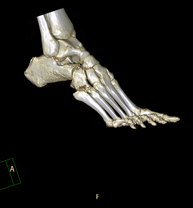

- TC de turmell-peu

Exploració radiològica que mitjançant un sistema de raigs X i detectors que giren al voltant del pacient i que reconstrueixen les imatges per ordinador (TC Multidetector), permet l'estudi detallat dels ossos, els músculs i les articulacions del turmell i el peu. - TC d'estudi rotacional EEII (Bàscula rotuliana, distància TA-GT)